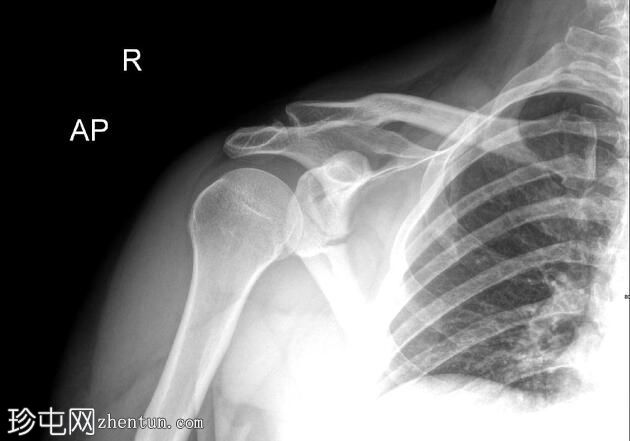

2.jpg

正面

右侧肩胛骨骨折,累及肩胛盂、肩胛颈和肩胛体。肱骨头与肩胛窝对位良好,提示无肩关节脱位。

肩部和肩胛骨周围有弥漫性软组织肿胀。

本例X光片显示骨折累及肩胛盂、肩胛颈和肩胛体,提示力量显著通过肩胛带传递。肩胛盂受累尤为重要,因为它可能损害盂肱关节的稳定性和关节的一致性。

肩关节无脱位且肱骨头排列完整是有利的发现。然而,由于解剖结构复杂且可能在关节内延伸,建议进行CT扫描以更好地明确骨折形态并指导手术计划。